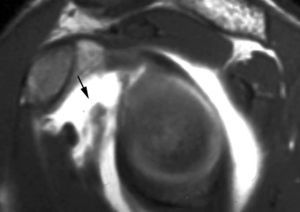

POLPSA (posterior labral periosteal sleeve avulsion)

Esta lesión se asemeja a la ALPSA, pero ocurre en el borde glenoideo posterior. El LG se halla desplazado hacia dentro y por detrás del borde glenoideo posterior. El mecanismo de producción del POLPSA es una dislocación posterior, y por tanto se puede encontrar también un Hill Sachs invertido19 (fig. 14).

. Artrorresonancia axial T1 con supresión grasa donde se observa una rotura del labio glenoideo posterior con desplazamiento posteromedial (flecha). Nótese la situación del labio glenoideo en comparación con una rotura sencilla, no desplazada, que se observa en la figura 13. Obsérvese la presencia de una lesión de Hill-Sachs invertida (cabezas de flecha), en relación con una dislocación posterior con reducción.Lesión de Bennett